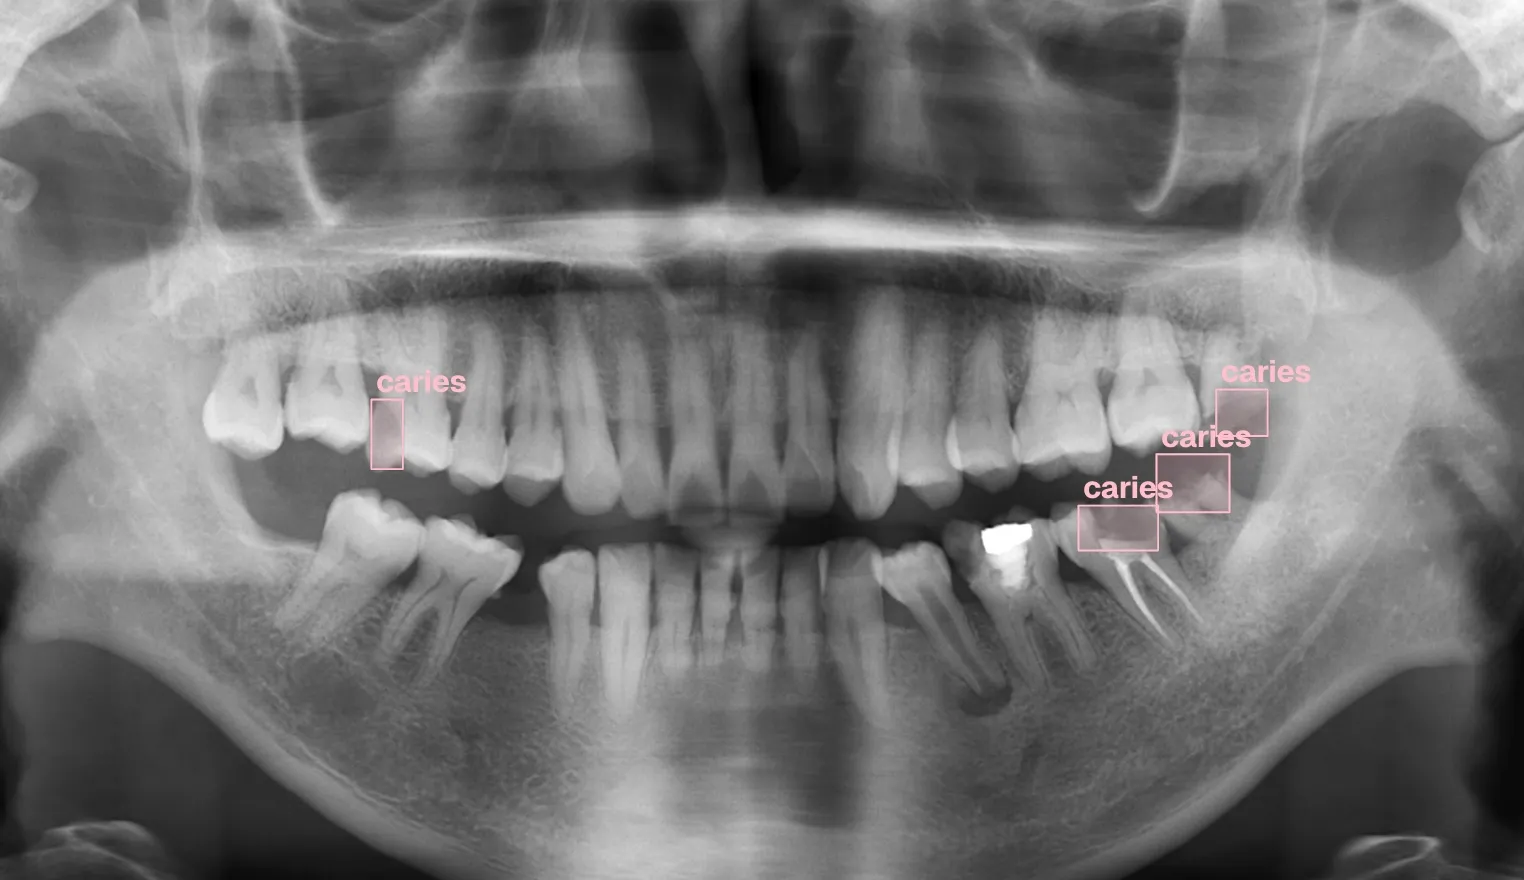

- Advanced oral surgery techniques

- Complex restorative procedures

- Emergency dental care